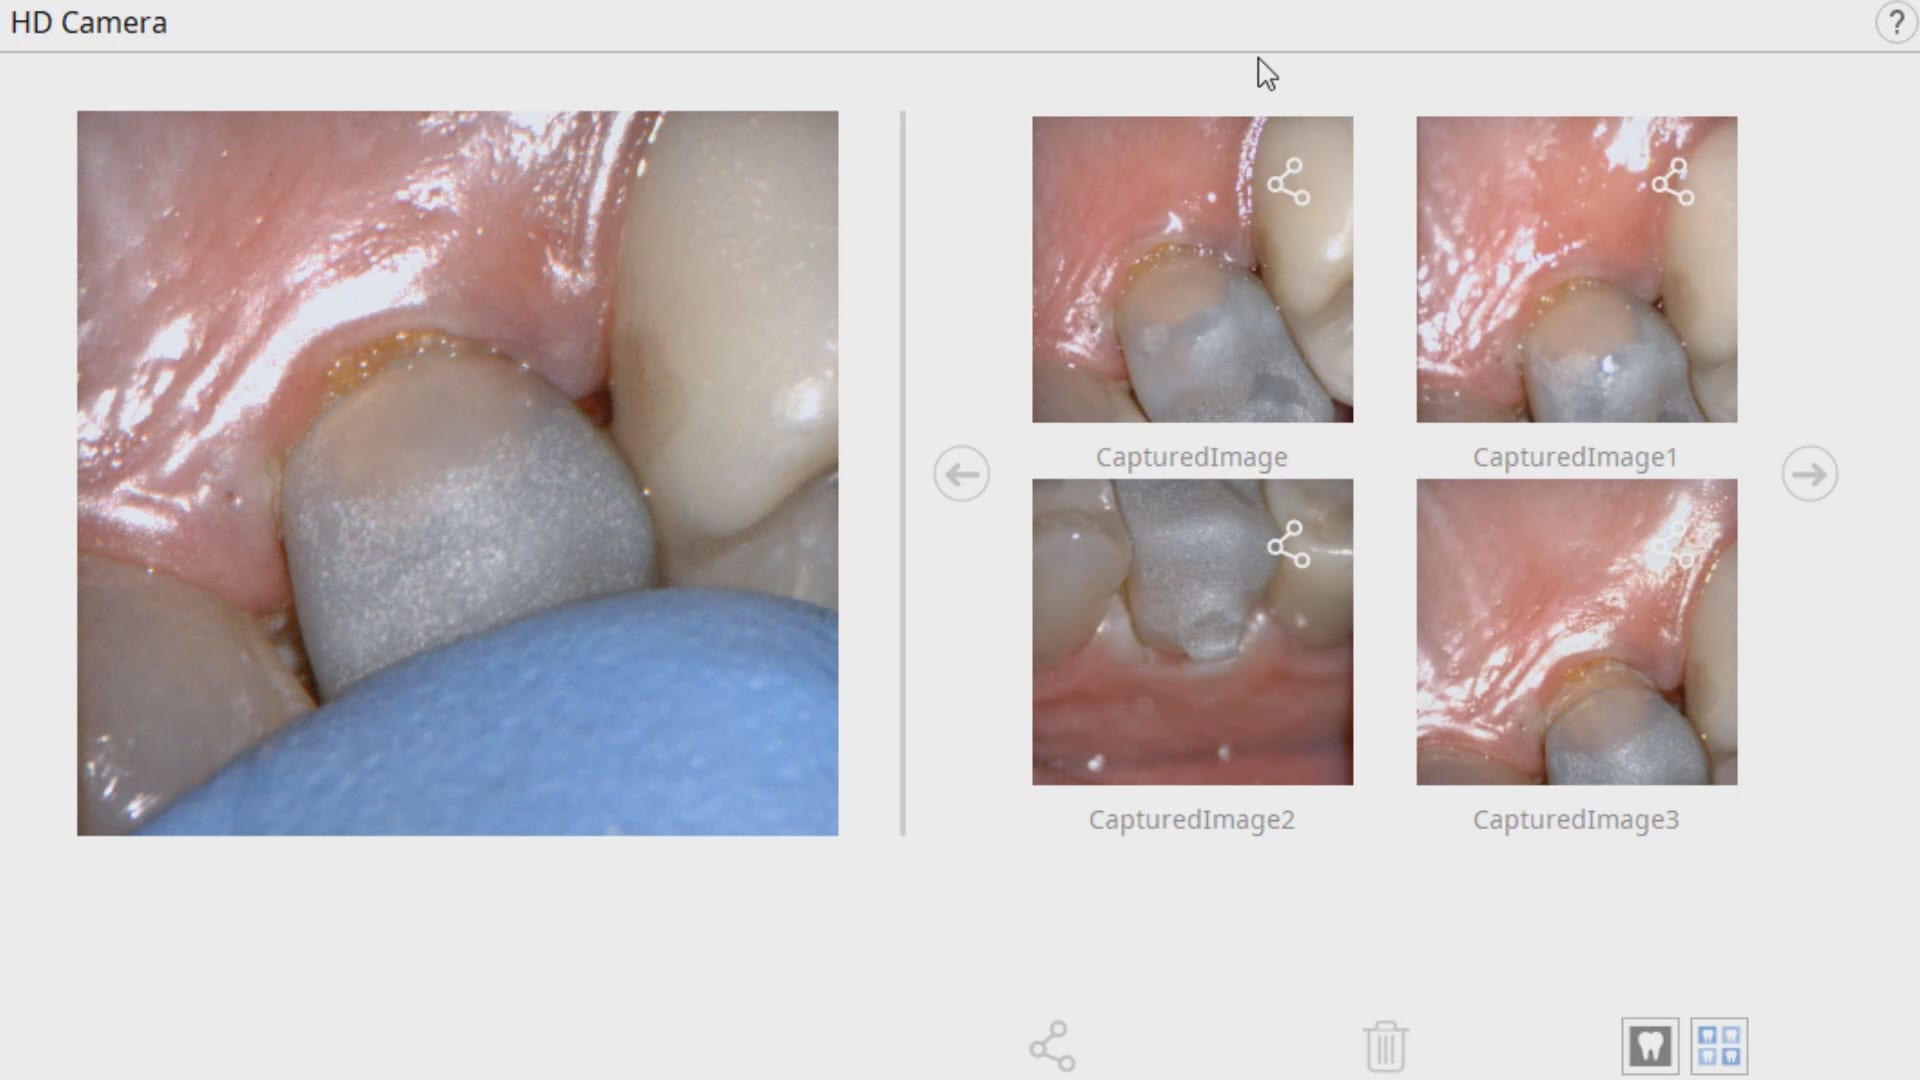

In this clinical case a patient lost a pre-existing crown. The remaining tooth structure had recurrent decay and a new crown was warranted.

After anesthesia was administered, the clearance from opposing dentition was assessed. The preparation was reduced to accommodate the necessary thickness of the material.

Once adequate clearance was achieved an Optragate was placed and an isolite was used to isolate the area. The preparation was scanned and then the lower arch was captured. The buccal bite was then taken to along the arches together